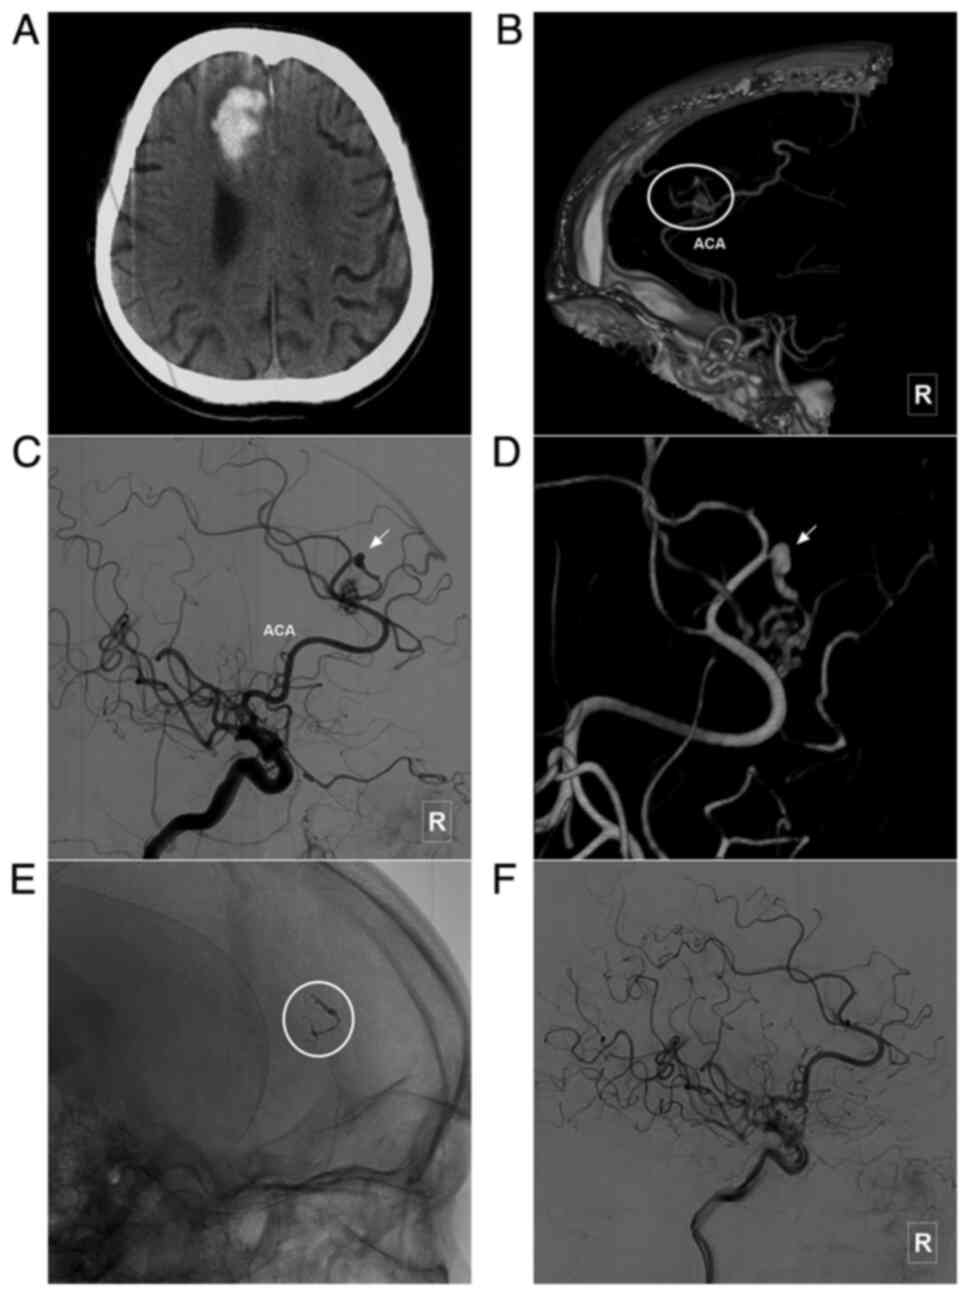

Figure 4

Typical case of a type II BAVM with flow-related aneurysm in the ACA branch. (A) Head CT scan illustrating a hemorrhage in the right frontal lobe. (B) Head CTA scan illustrating a BAVM supplied by the branch of the ACA (encircled area). (C and D) Angiogram of the right internal carotid artery in (C) lateral view and (D) three-dimensional angiogram of the right internal carotid artery indicating that the BAVM is supplied by a single branch of the ACA, with a dissecting aneurysm (arrow) at the beginning of supplying artery. (E) X-ray of the cranium illustrating Onyx casting (encircled area). (F) Angiogram of the right internal carotid artery following treatment indicating the complete embolization of the BAVM and flow-related aneurysm. ACA, anterior cerebral artery; BAVM, brain arteriovenous malformation; CT, computed tomography; CTA, computed tomography angiography; R, right.